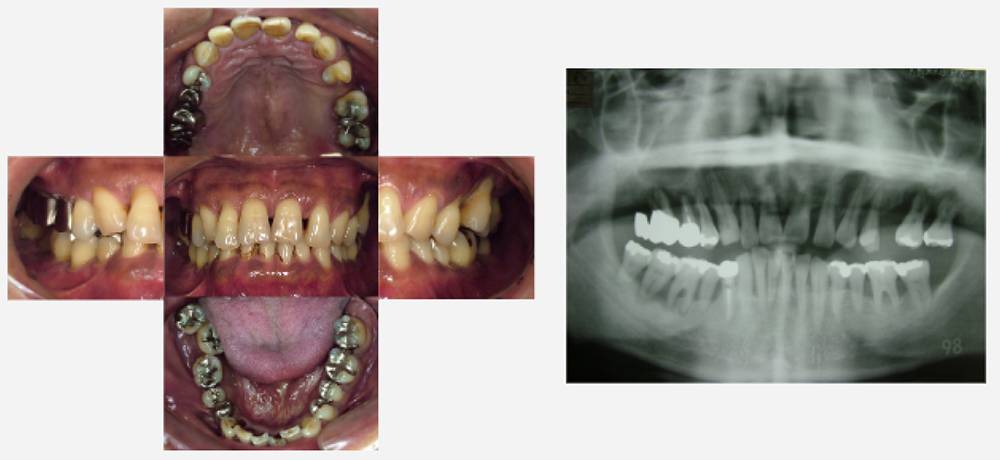

治療前治療後

| 治療内容 | インプラント奥歯1本・根管治療・矯正治療(圧下) |

|---|---|

| 患者様の年齢 | 40歳 |

| 患者様の性別 | 男性 |

| 治療期間 | 1年 |

| 治療回数 | 矯正治療合わせて50回程度 |

| 治療費用 | 根管治療1歯6万円/インプラント治療1歯50万円 矯正治療:1歯 10万円 |

| 治療で得られるメリット |

|

| 治療する際に起こる リスク・副作用 |